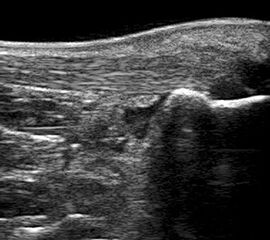

Peronealsehnenläsion

Lagerung: Rückenlage, Innendrehung des Beines

Schnittführung: TS und LS hinter dem Außenknöchel beginnen und die beiden Peronäalsehnen bis zur Basis des Metatarsale V durchmustern, für Longus-Sehne auch plantare Untersuchung in TS und LS (Abb. 39).

Referenzstrukturen: Fibulahinterkante, Basis Metatarsale V.

Befunde: Halophänomen und echoarme Verdickung bei akuter Tendinopathie, zunehmend inhomogen und echogen bis hin zu Teilrupturen bei chronischem Verlauf. Für die Erkennung von Teilrupturen sind TS in verschiedener Höhe besonders wichtig. Bei komplettem Riss zeigt sich der Sehnenstumpf wie eine Spargelspitze (Abb. 40). Der retrahierte Sehnenstumpf ist von Flüssigkeit und Hämatom umgeben.

Ein Teilriss der Peronaeus brevis Sehne mit Invagination der Peronaeus longus Sehne kann beim Peronaeal Tendon Split Syndrom beobachtet werden (Abb. 41 und 42).